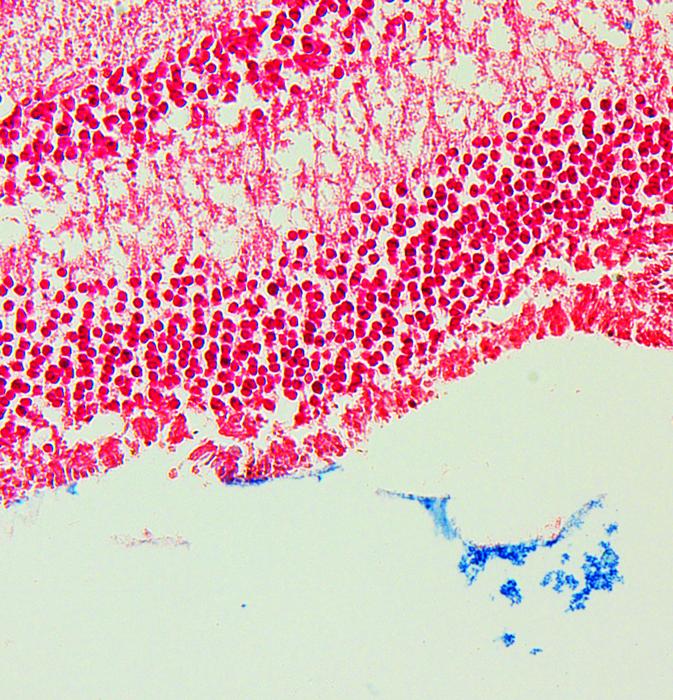

The answer to this problem may lie in controlling iron levels. The researchers found that patients with OT had a decreased iron concentration in the vitreous humor compared to patients with other eye diseases. Furthermore, when they examined sections taken from the eyes of mice with toxoplasmosis, they found increased iron uptake into the retinas.

Further investigation identified ferroptosis, a form of iron-associated cell death, in the affected areas of the retina. As the retina is a key part of the eye that converts light into electrical signals from a person’s optic nerve to their brain, cell death may explain why some patients are blinded by OT.